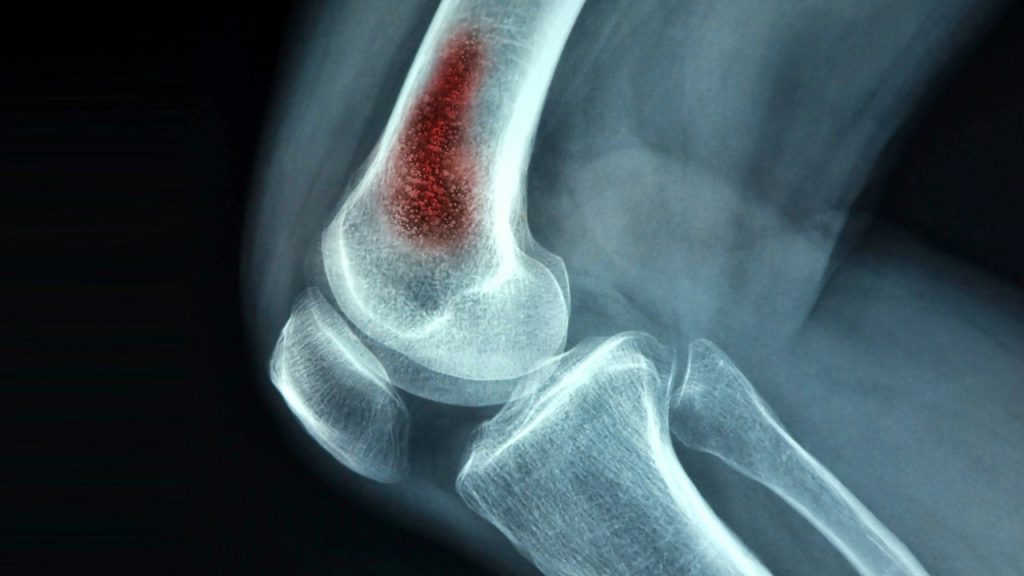

Osteomyelitis (OM) Causes, Symptoms, Risk factors, and Treatment